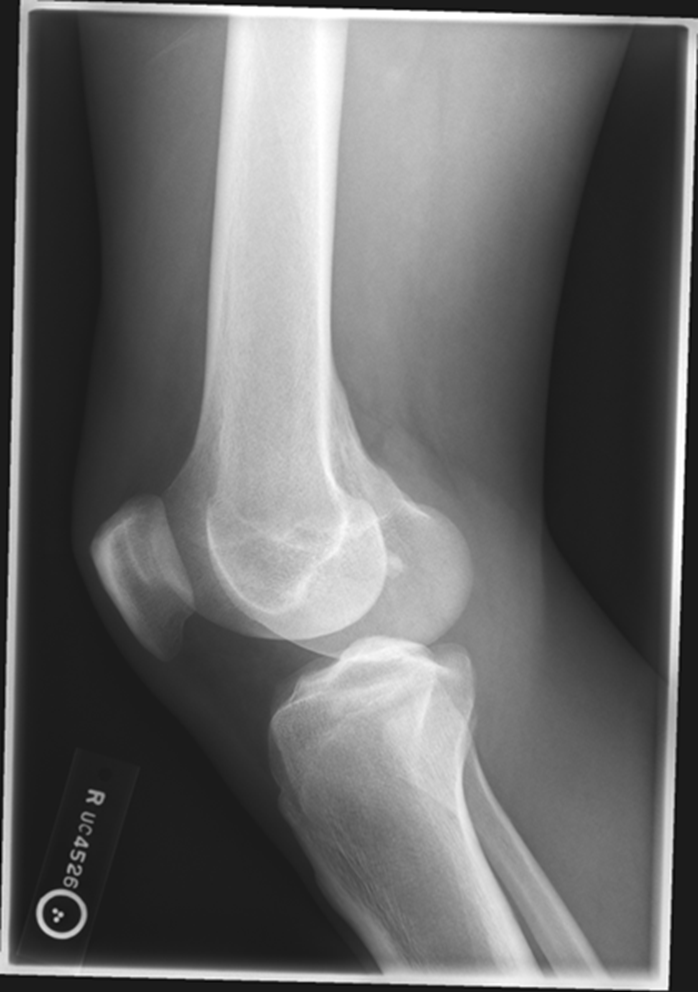

Trauma and Non-Trauma Lateral Knee (Mediolateral)

•Evidence of proper collimation and the presence of a side marker placed clear of the anatomy of interest

•Knee flexed 20 to 30 degrees in true lateral position as demonstrated by femoral condyles superimposed (locate the more magnified medial condyle)

•Anterior surface of medial condyle closer to patella results from over-rotation toward the image receptor (IR).

•Anterior surface of medial condyle farther from patella results from under- rotation away from the image receptor (IR).

•Inferior surface of medial condyle caudal to lateral condyle results from insufficient cephalad central ray (CR) angle.

•Inferior surface of lateral condyle caudal to medial condyle results from too far cephalad CR angle.

•Fibular head and tibia slightly superimposed (over rotation causes less superimposition, and under rotation causes more superimposition)

•Patella in a lateral profile

•Open patellofemoral joint space

•Open joint space between femoral condyles and tibia

•Bony trabecular detail and surrounding soft tissues

over-rotated fibular head is not touching

Patellofemoral joint space is not open (Condyle is in it)

Remove soft tissue of another leg

The medial condyle is closer to the patella it is over rotated

Lateral condyle is lower, too much tube angle

Rotation, fibula is under! Which means it is under-rotated. The condyle is in the patella femoral space, the abductor tubercle (medial condyle) , medial condyle is posterior. Central Ray is too superior. NOT ENOUGH